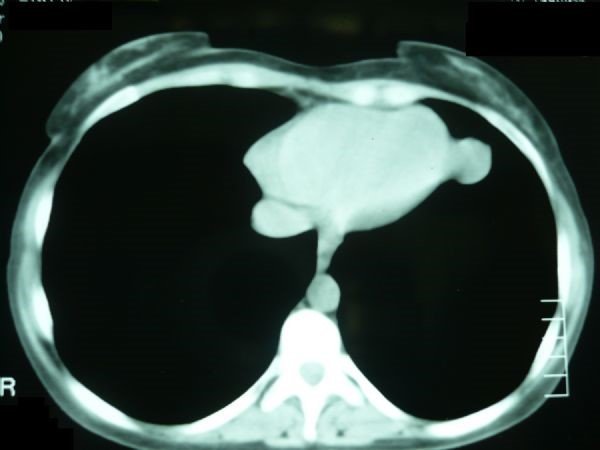

• Bronxial və enterik sistlərin diaqnozu adətən çıxarıldıqdan sonra dəqiqləşir. Perikardial sistlərin diaqnozu görüntüləmə ilə dəqiqləşdirilə bilir (Şəkil 23), lakin diferensiasiya çətinliyi və simptomatik olanlarda cərrahi eksiziya lazım gəlir.

Şəkil 23. KT. Perikardial sist